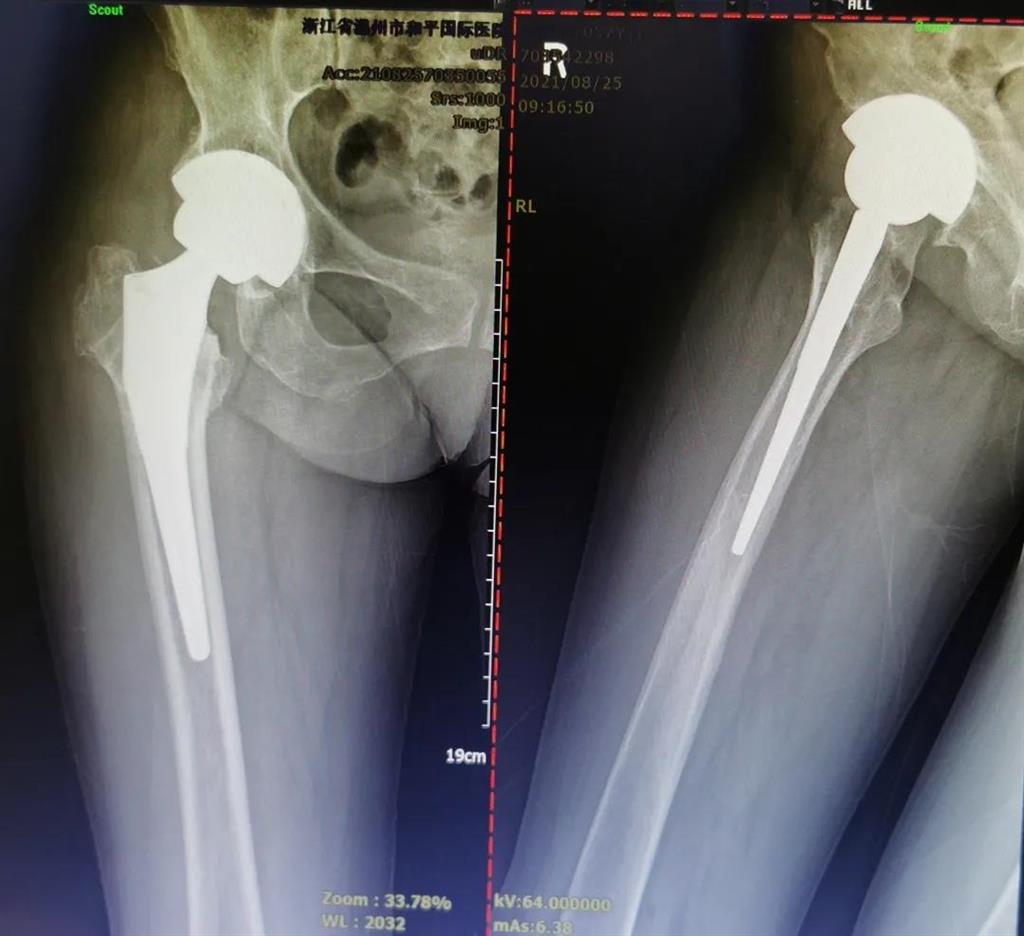

(△術前影像,右股骨頸骨折內固定術后股骨頭壞死)

(△做完“右股骨頸全髖關節置換術”后的影像)